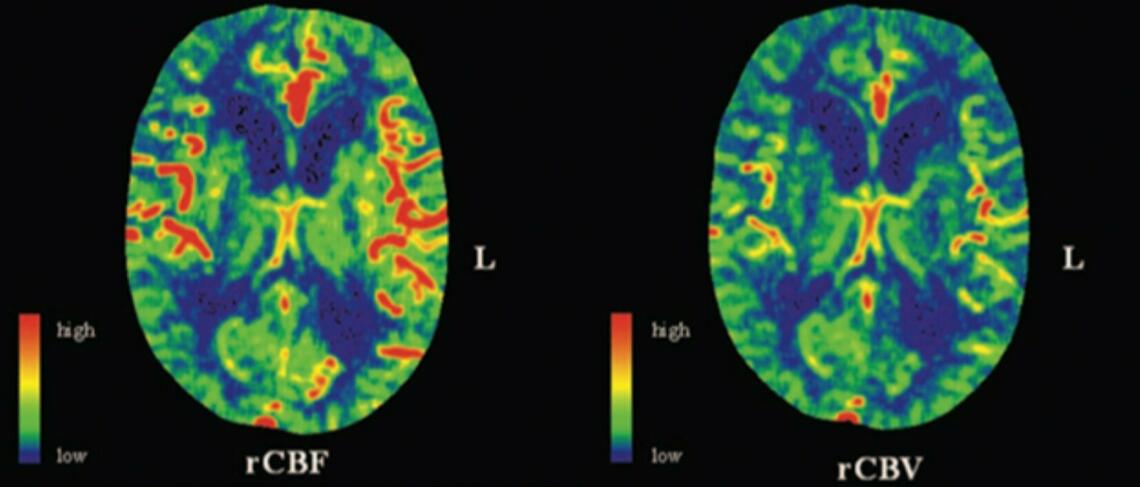

An example of vascular dynamics imaging obtained through CT Perfusion imaging. These brain maps show the relative amount of cerebral blood flow (left) and cerebral blood volume (right).

Although seizures are classically associated with abnormal electrical activity, recent work has suggested that there is also disrupted vascular activity following a seizure. Our lab has been involved in ground-breaking recent work that found significant and long-lasting blood flow reductions in the brain following a seizure. In humans, we have been able to detect reductions in blood flow using arterial spin labelling MRI that lasts upwards of an hour following a seizure and tend to co-localize with the region of seizure onset. We have been able to show similar results in less expensive and more readily available methods of neuroimaging such as CT Perfusion, allowing these blood flow changes to be studied in a broader population.